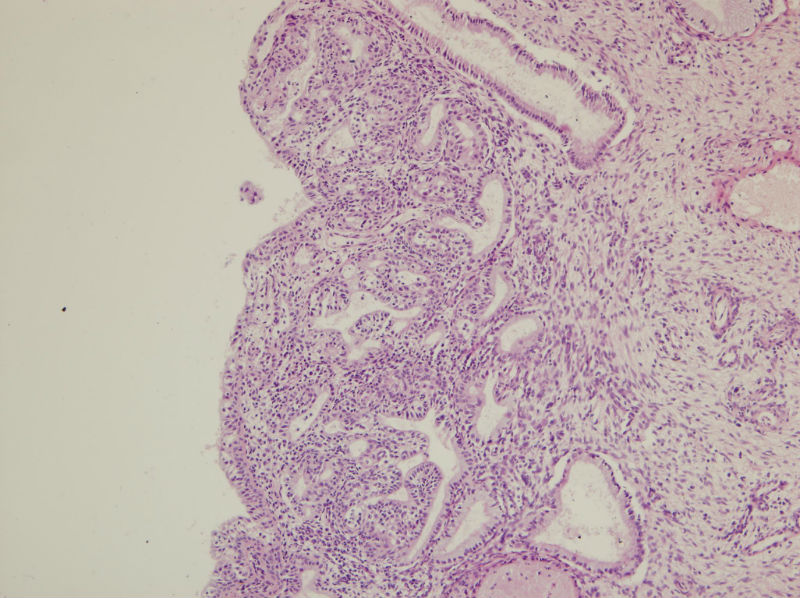

45岁,宫颈息肉?请老师指教

• 45岁,宫颈息肉?请老师指教图1

图1

慢性炎,腺体有鳞化

宫颈及宫颈内膜息肉,腺体增生及鳞化,鳞化跟中药没有关系,跟炎症刺激有关系。

宫颈息肉伴腺体鳞化,微腺体增生

宫颈息肉,伴有微小腺体增生。

宫颈息肉伴腺体的鳞化,我个人感觉息肉的分型比较复杂,有的地方存在宫颈腺体增生型,有些地方血管型,还有纤维型也可见。

宫颈息肉伴鳞化和微腺体增生

宫颈息肉伴糜烂,局部腺体及黏膜上皮鳞状上皮化生。至于说具体分型,与临床治疗和预后都没有关系,可以不分。

Benign endocervical polyp with SM and MGH. You do not need classify benign endocervical polyp because it has no impact on clinical management.